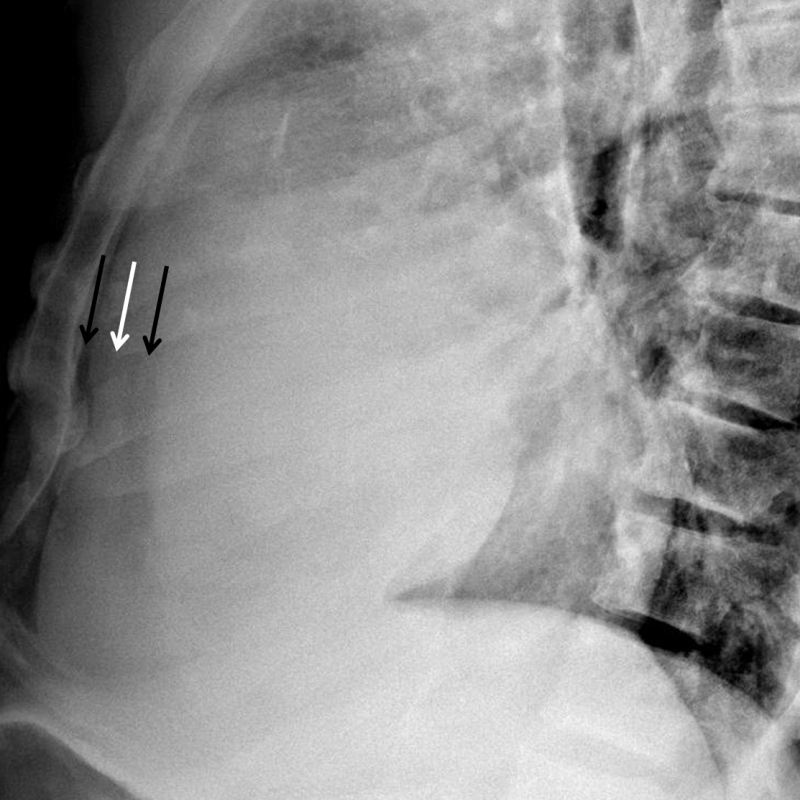

Age: 24

Sex: Female

Indication: Chest pain, dyspnea

Sample ReportFindings most suggestive of a moderate to large pericardial effusion. Suggest correlation with echocardiography.